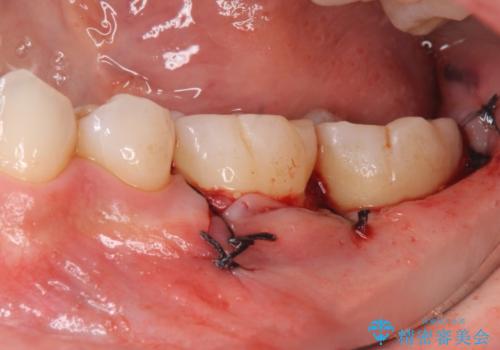

2:歯周外科手術を行う

3:2週間後に抜糸